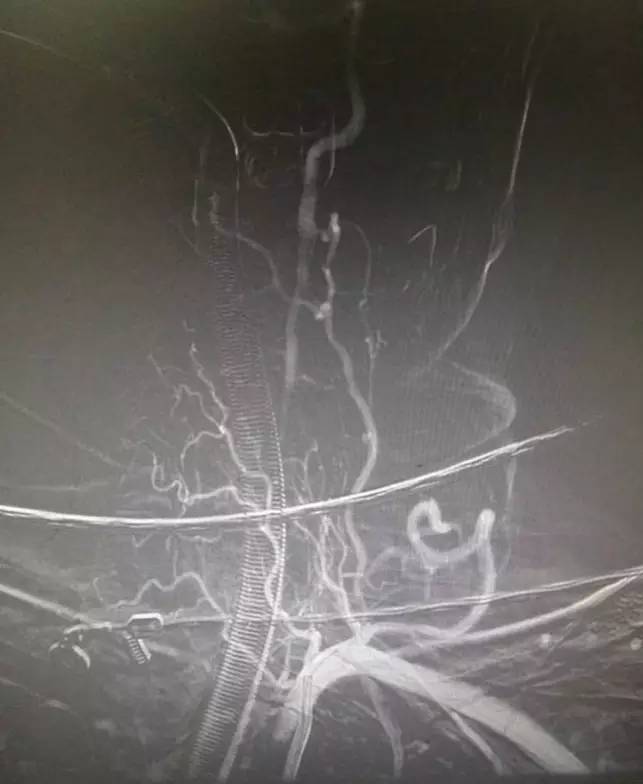

▼支架释放后,右大脑后及小脑上显影同时看到基底动脉的血栓,拉栓一次就再通。

此时手术是否结束?内心又开始纠结了,贪心的本性又暴露,如果左椎是急性闭塞那么打通之后给患者又多加一个保险,这样以后万一右椎有什么三长两短那么左椎还可以救命所以决定开通左椎:费了好大劲通过微导丝进入椎开口内,向上不能通过闭塞段考虑为陈旧性闭塞,遂即放弃开通!术后欣慰宁维持!